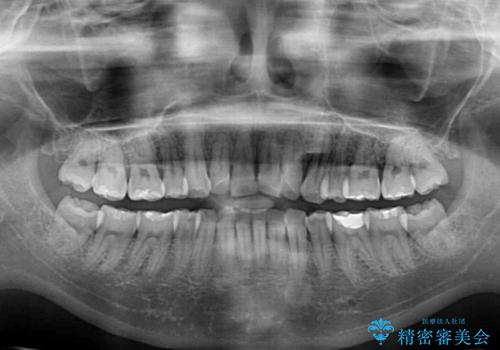

- 上の前歯の出っ歯を治したいとのことで来院された患者様です。

後戻りによる再矯正というもともあり、インビザラインを希望されていました。

上顎の歯は後方移動とIPR(歯と歯の間を削る)によって口元が引っ込むように、下顎は歯列全体の拡大とIPRによって上顎とバランスよく咬み合うように設計し、インビザラインにより治療を行うこととしました。

治療を開始して暫くして、勤務先から2年以上帰国することができず、それまでの移動がほとんど後戻りしてしまい、帰国後に再度後戻りをリカバリーするための治療を行うこととなりました。

5年以上の治療期間がかかりましたが、気になっている部分を改善することができました。